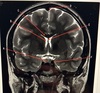

Match 1. Corpus callosum 2. Tentorium 3. Lateral ventricle 4. Thalamus 5. Medulla oblongata 6. 4th ventricle

A. Lateral ventricle B. Corpus callosum C. Thalamus D. Tentorium E. 4th ventricle F. Medulla oblongata